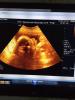

@anneta28, а это 3д УЗИ? Я думала после 30 недель сходить, чтоб личико малыша было видно, вот сомневаюсь, а видно ли его будет😆

@zabortseva92, в жд больнице, там такая клевая женщина!! Отдала вроде 800, а может больше, не буду врать, муж рассчитывался я была на эмоциях. Фото и видео прилагается